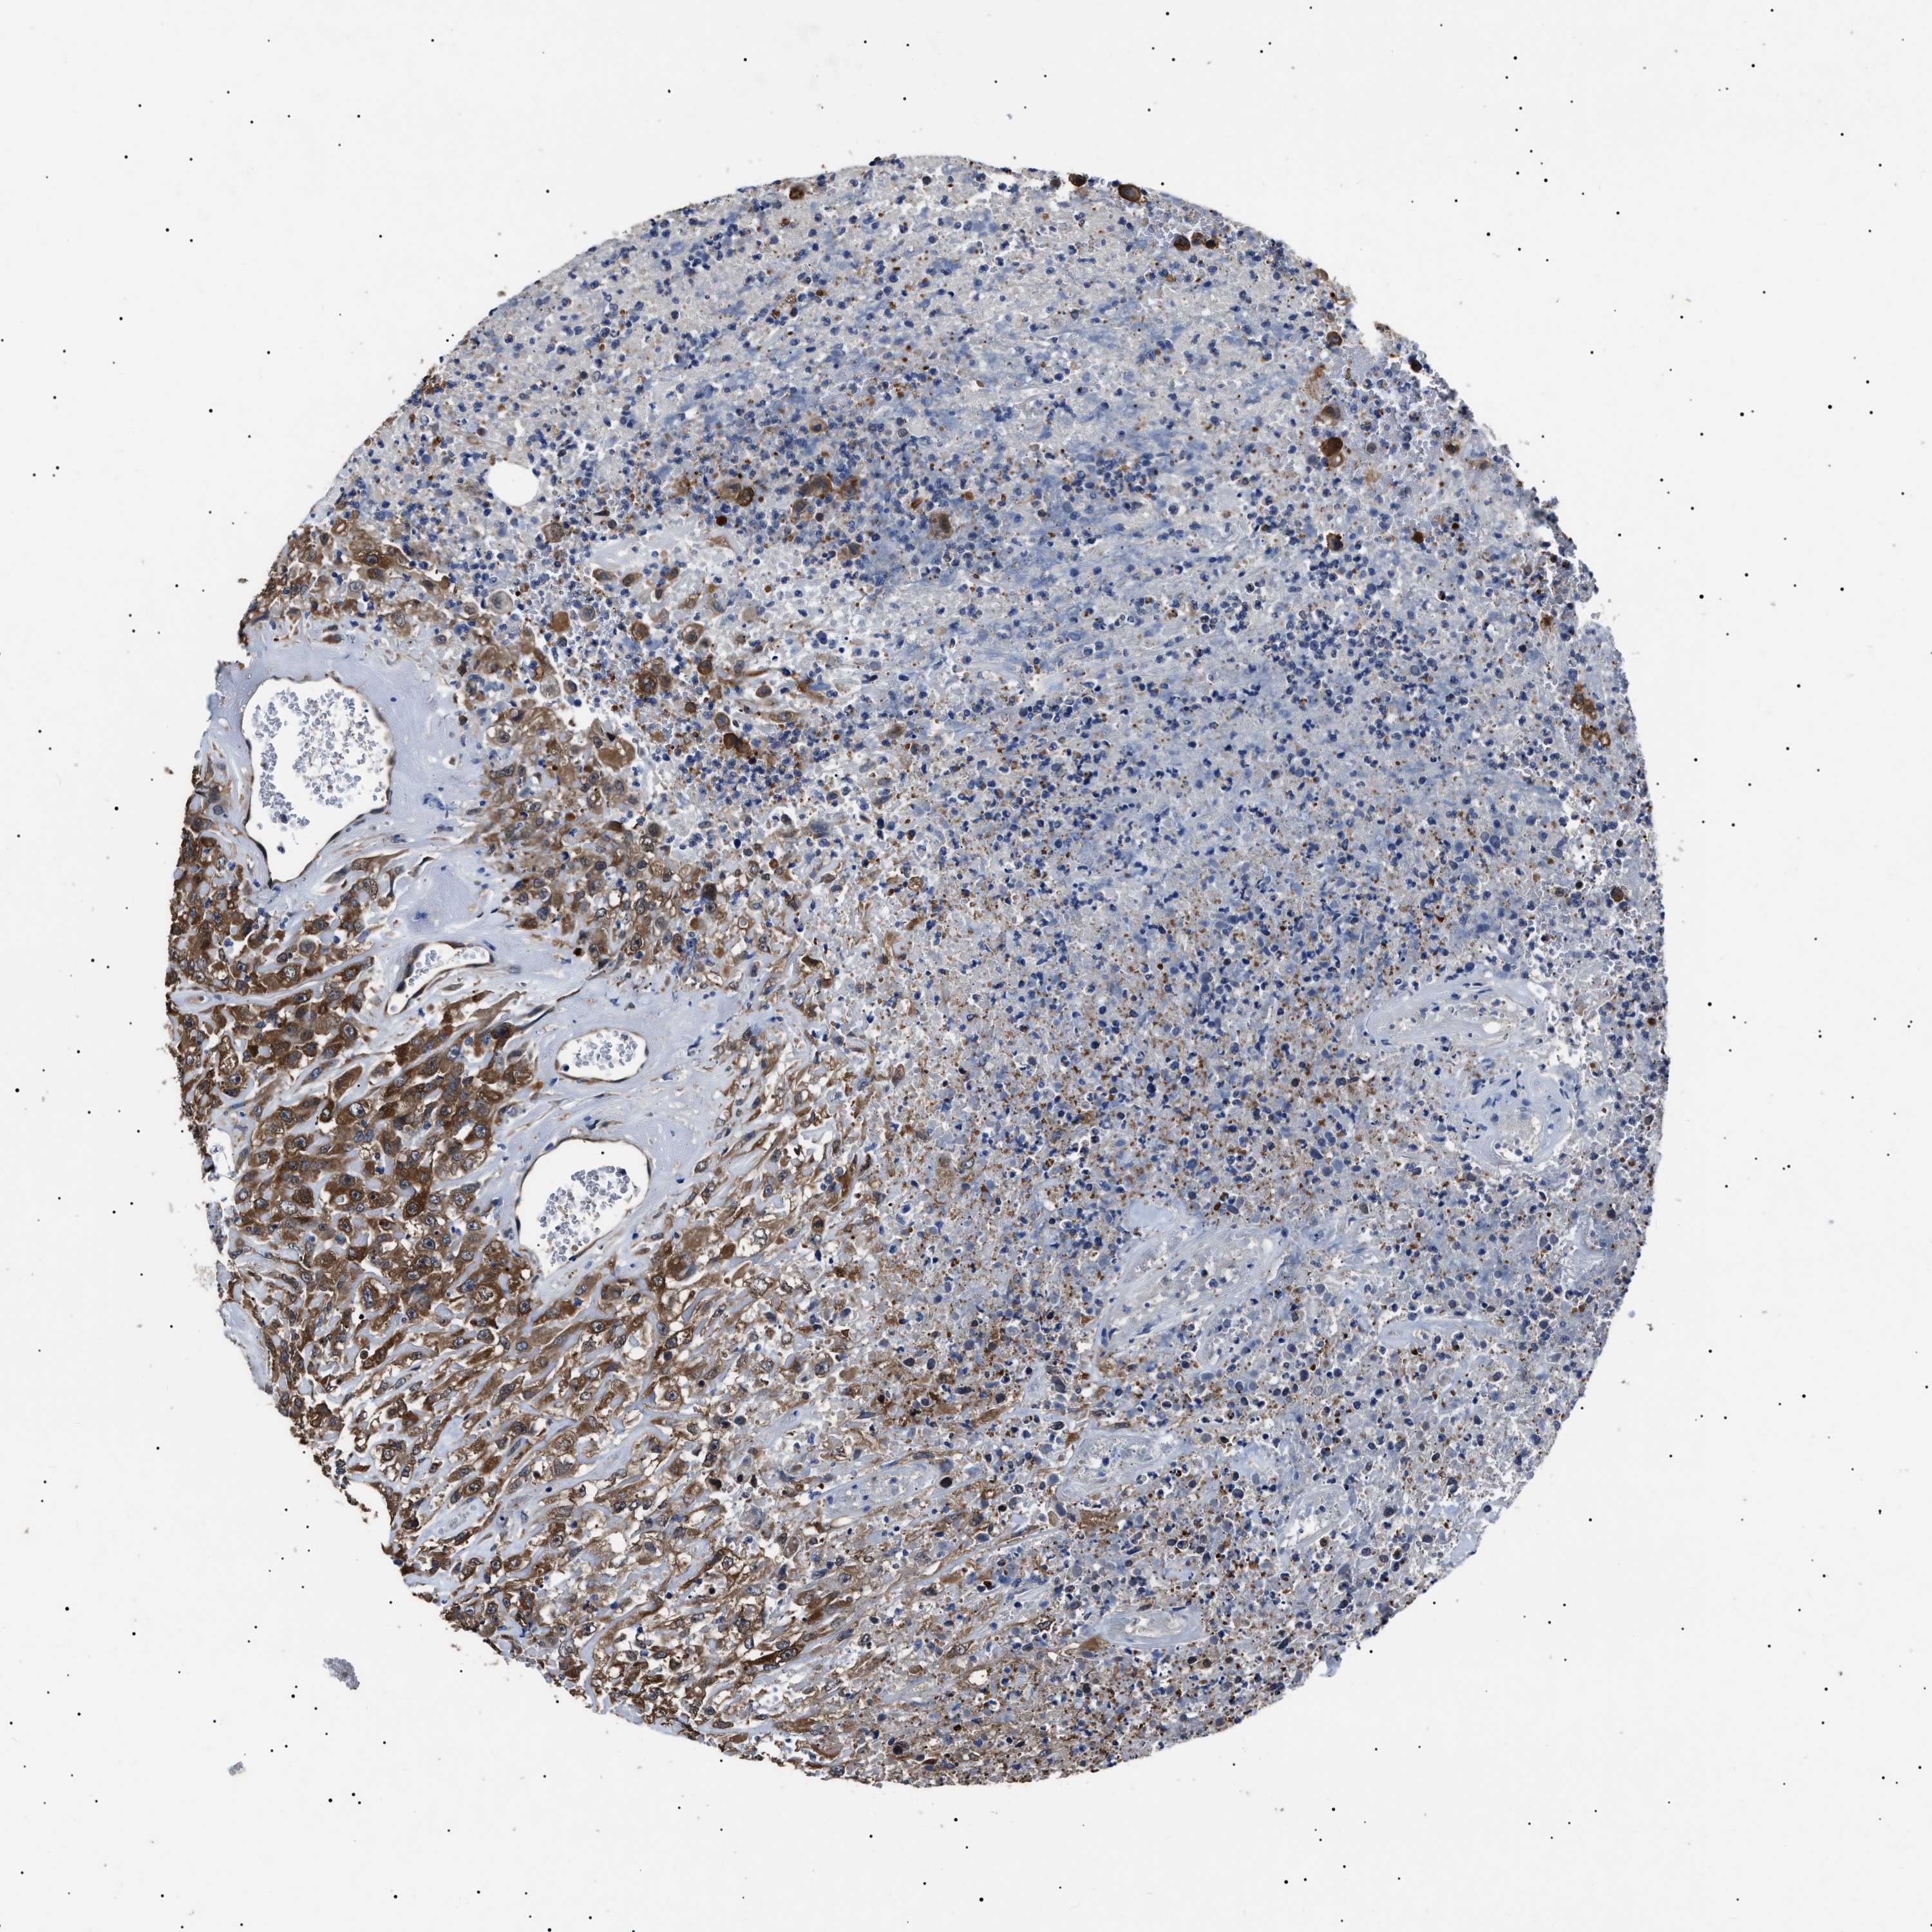

UROTHELIAL CANCER - Protein expressioni

A mouse-over function shows sample information and annotation data. Click on an image to view it in a full screen mode. Samples can be filtered based on level of antibody staining by selecting one or several of the following categories: high, medium, low and not detected. The assay and annotation is described here.

Note that samples used for immunohistochemistry by the Human Protein Atlas do not correspond to samples in the TCGA dataset.

Antibody stainingi

Antibody staining in the annotated cell types in the current human tissue is reported as not detected, low, medium, or high, based on conventional immunohistochemistry profiling in selected tissues. This score is based on the combination of the staining intensity and fraction of stained cells.

Each image is clickable and will lead to virtual microscopy that enables deeper exploration of all samples and also displays staining intensity scores, fraction scores and subcellular localization as well as patient and tissue information for each sample.

Antibody HPA018520

Antibody HPA021051

Antibody HPA029426

Urothelial carcinoma, Low grade

Urothelial carcinoma, High grade